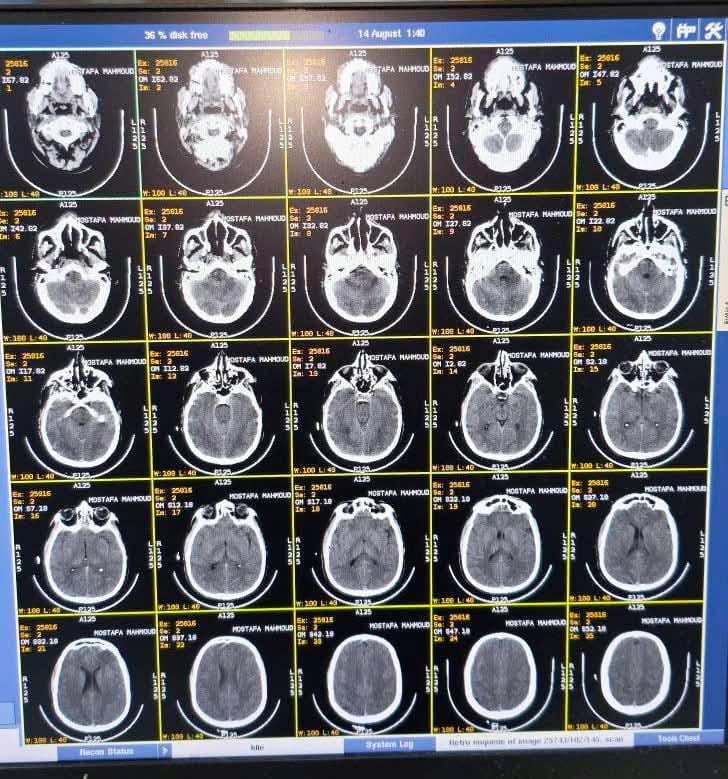

ارتجاج بالمخ وجروح قطعية وإصابات خطيرة لمصطفى

ذهبوا به إلى مستشفى الحوامدية التي رفضت استقباله لخطورة حالته وعدم توافر رعاية مركزة مخ وأعصاب لديها، لينتقلوا به إلى مستشفى أم المصريين التي رفضت هي الأخرى استقباله لخطورة حالته بعدما شاهدوا الأشعة المقطعية وعدم وجود رعاية مركزة مخ وأعصاب لديها، لينتهي به المطاف فجرًا بالرعاية المركزة مخ وأعصاب بمستشفى القصر العيني ما بين الحياة والموت، يعاني من ارتجاج بالمخ بمستشفى الطوارئ الجديدة بالقصر العيني، بعدما تم عمل اللازم طبيًا وتشخيص حالته بقطع غائر وجائر بالرأس أدى لارتجاج بالمخ والعديد من الكدمات والسحجات والضربات في الظهر والكتف والرأس.

هذا الشاب مصطفى الذي حتى الآن ما بين الحياة والموت، حيث يعاني من ارتجاج بالمخ إثر الضرب المبرح وجرح قطعي غائر بالرأس وكدمات وسحجات شديدة بالظهر وضربات بالرأس وفقدان القدرة على الكلام مع رعشة شديدة، هذا الشاب ينام في سرير المرض، بينما هؤلاء المجرمون يعيثون في الأرض فسادًا يتمتعون بالحرية وهو سجين المرض، وهم يتحركون في الشوارع، بينما هو وزوجته المريضة المعتدى عليها حبيسان سرير المرض.